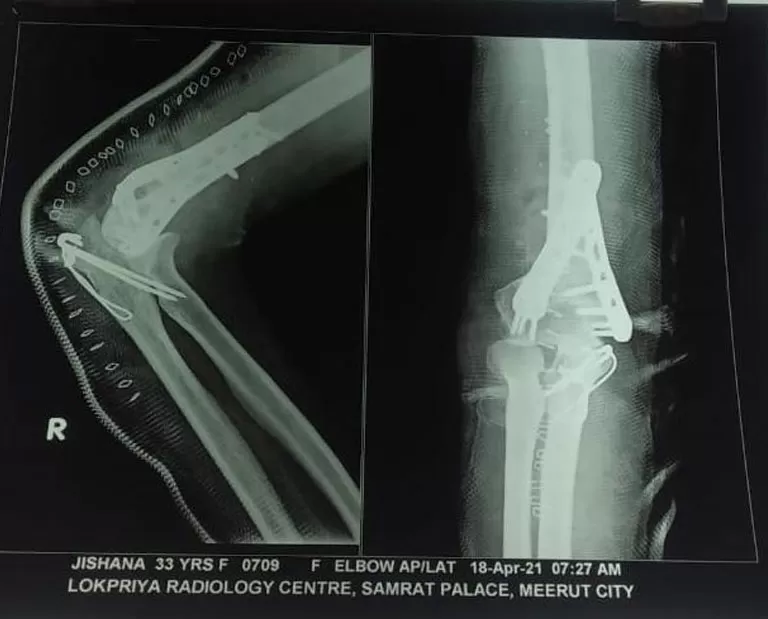

Mrs. Zeeshana

Name: Mrs. Zeeshana

Date of Operation: 03 Feb 2020

Age: 33 Years